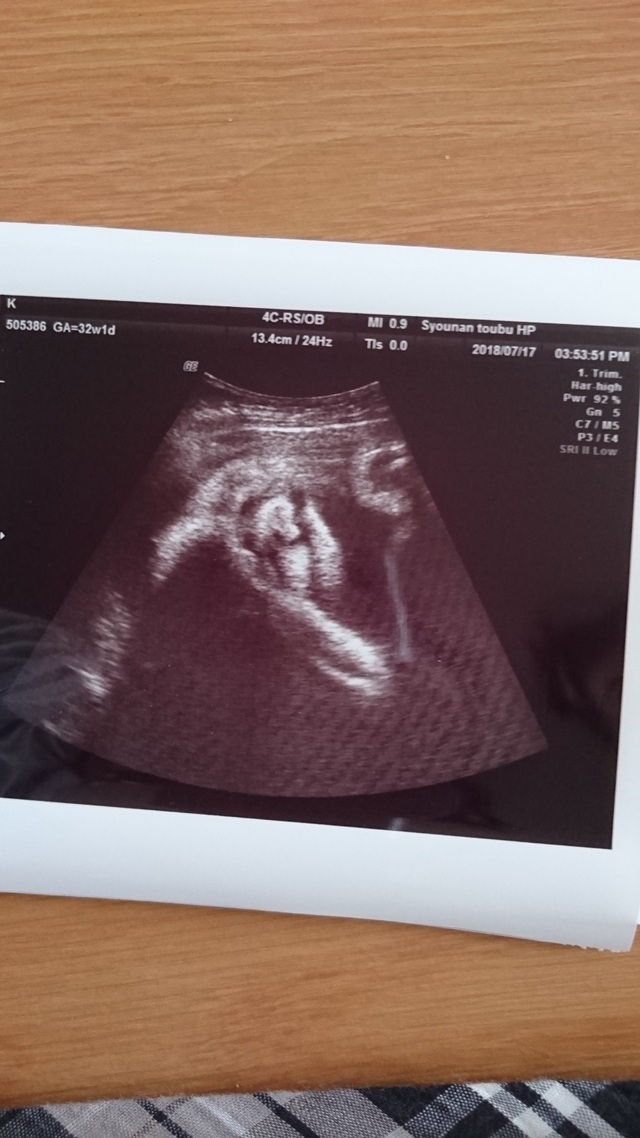

32週0日(32w0d・女の子)|えみちん99 さん(25歳)

エコー写真撮影時のエピソード:

週数よりもいつも小さめだと言われており、心配でしたが、元気だと言われて安心していました。エコーの時は寝てることが多かったけど、いつもお顔は見せてくれていたので、うれしかったです。月に1回のエコーで成長を見るのが楽しみでした。